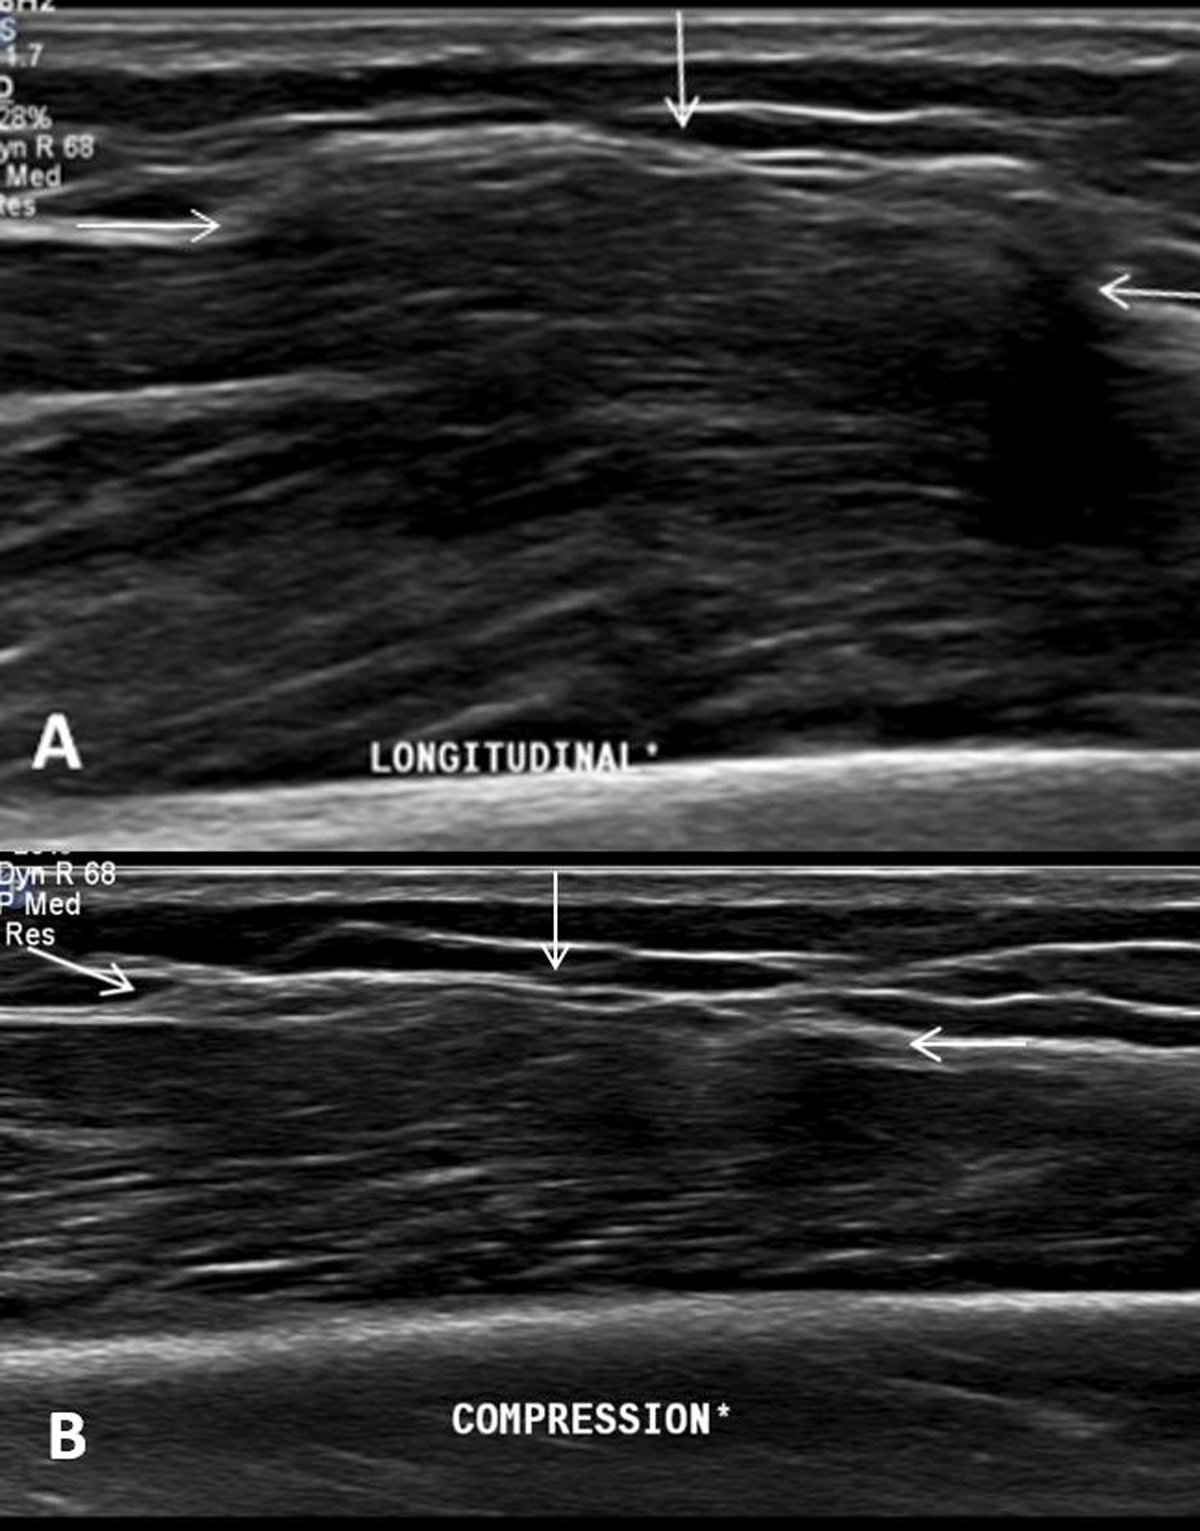

A 42-year-old woman was referred for magnetic resonance imaging (MRI) for evaluation of a painless soft-tissue swelling on the lateral side of the lower leg. The lesion had been present for many years and was more prominent in standing position. There was no history of trauma. A skin marker was placed at the soft-tissue lump in standing position. MRI showed subtle bulging of the contour of the peroneus longus muscle belly (Figure 1A, white arrow). The lesion was iso-intense to muscle tissue on all pulse sequences. There was no volume increase upon peroneus longus muscle contraction in supine position (Figure 1B). Subsequent dynamic ultrasound in standing position confirmed protrusion of peroneus longus muscle tissue (white arrow) through a fascial defect (Figure 2A). The lesion was barely visible in supine position and could be completely reduced upon compression with the ultrasound probe (Figure 2B). The muscle protrusion appeared more pronounced in standing position (supplementary video). Clinical examination and imaging were characteristic of peroneus longus muscle herniation.

Figure 2

On clinical examination, the lesion usually presents as a painless palpable swelling and is more prominent and harder upon muscle contraction. In some cases, it may be painful during exercise. Dynamic ultrasound is the preferred imaging modality when muscle herniation is suspected. Ultrasound during contraction or in standing position demonstrates volume increase through the myofascial defect compared to ultrasound during rest. Extensive compression with the ultrasound probe may reduce the muscle protrusion. Therefore, a technique of graded ultrasound compression and alternated muscle relaxation is recommended. On dynamic MRI with muscle contraction and relaxation, a bulging muscle contour with a focal fascial disruption may be rarely seen. It is often not recognized due to its supine position. In an uncomplicated muscle herniation, the protruded muscle tissue demonstrates iso-intense signal intensity to non-herniated muscle tissue. Hyperintense signal in the herniated muscle tissue on T2-WI corresponds to muscle edema or fascial tearing [1].

Dynamic ultrasound (longitudinal view) in standing position shows disappearance of the muscle herniation upon compression with the ultrasound probe. DOI: https://doi.org/10.5334/jbsr.2294.s1